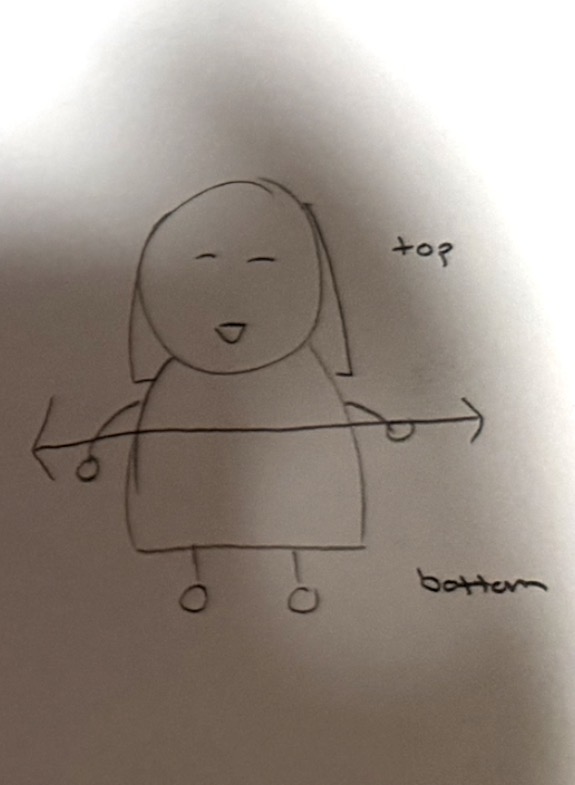

Transverse section

cut through middle of body to create a top and bottom

Superior

closer to the top of the body (standing up straight)

Inferior

below a body part or structure (standing up straight)